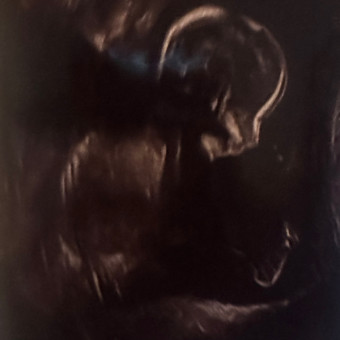

Christina & John Van Hook’s Baby Registry

Christina DiGiulian & John Van Hook

February 9, 2026